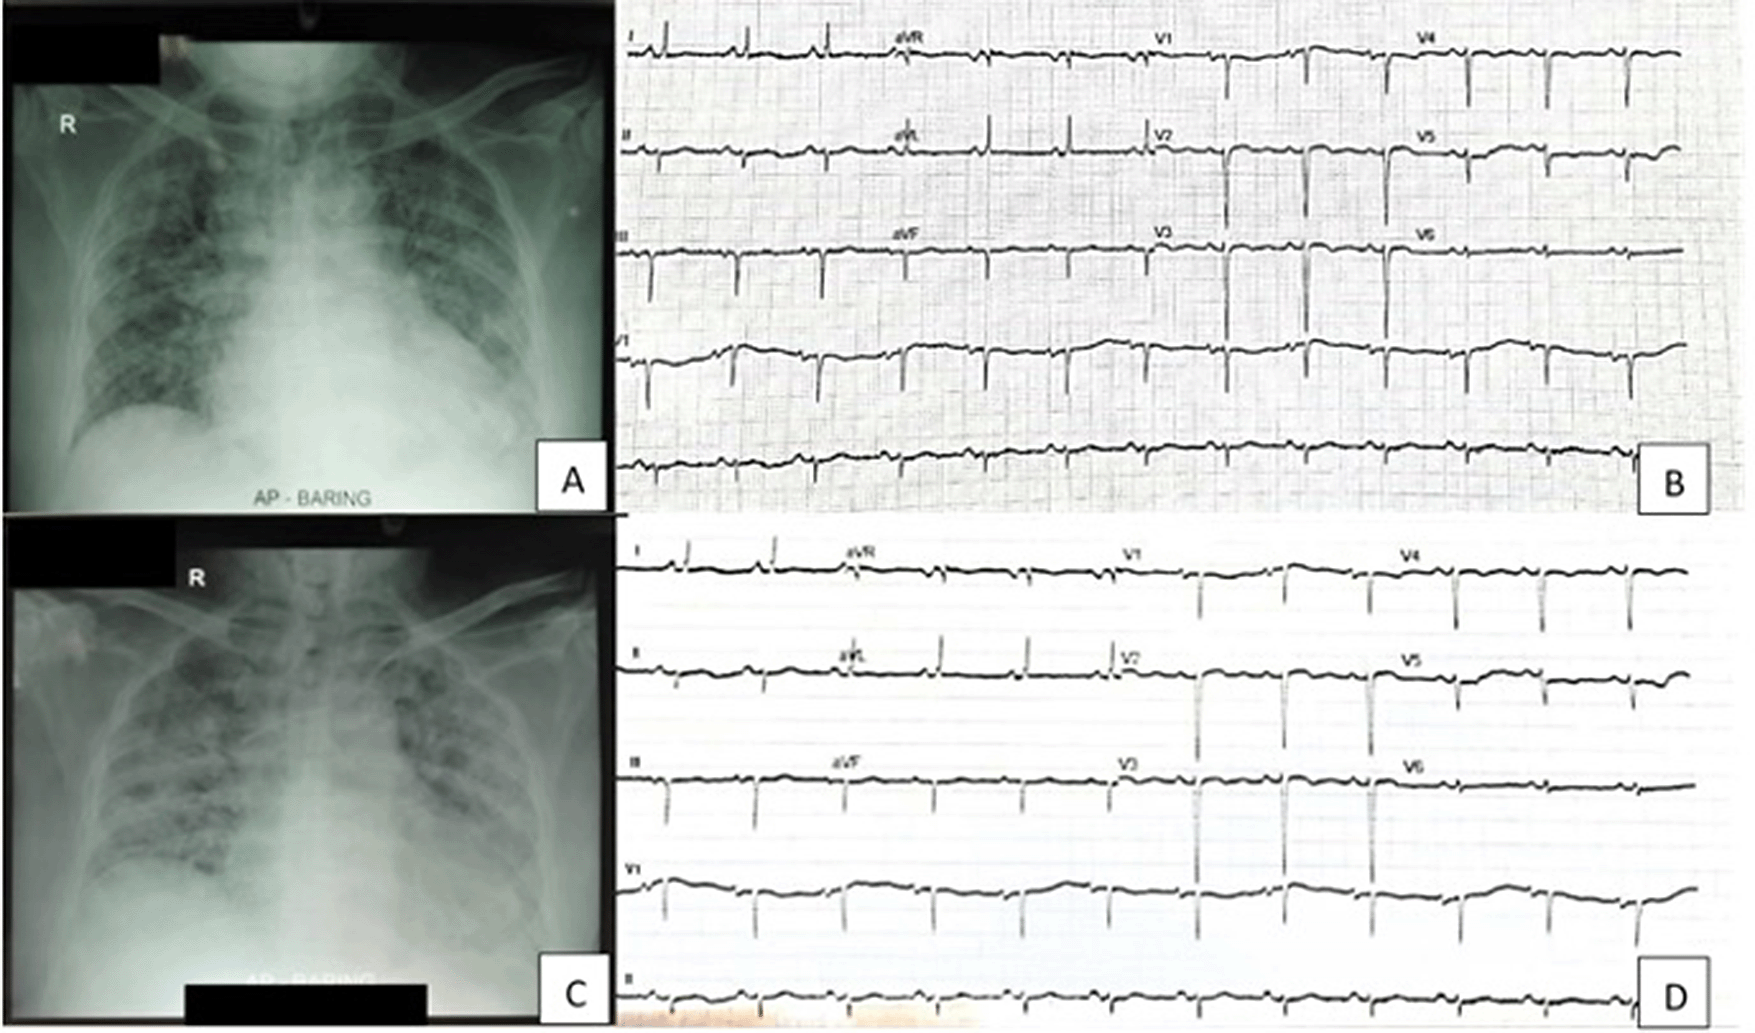

Comprehensive evaluations were performed, including ECG, COVID-19 antigen swab, laboratory examination, and chest radiography. His initial ECG showed normal sinus rhythm of 79 bpm, left axis deviation, with inferior OMI. Laboratory data showed increased CRP (195.3 mg/L), hypokalemia (3.2 mEq/L), respiratory failure, and respiratory acidosis. Chest radiography showed cardiomegaly and bilateral pneumonia. COVID-19 antigen swab was positive. Thus patient and family were consent for isolation and tracing procedure. As respiratory failure presented with severe ARDS (PaO2/FiO2 82 mmHg) and hypoxemia, the patient was informed about the need for performing an intubation procedure. Since our intensive care unit was occupied, we planned a referral to another facility. The patient and family refused it, so we hospitalized the patient in our lower care unit.

On the ninth day of admission, the patient seemed anxious with complaints of urinary pain. It showed that he had gross hematuria while he was on heparin therapy within targeted APTT. His vital signs showed BP 120/77 mmHg, tachycardia 110 bpm, and tachypnea 30 breaths per minute. Laboratory data showed significantly reduced thrombocytes (40,000 mg/L). Urine examination showed gross hematuria with leukocyturia (10–15 cells/field), nitrituria, and proteinuria (2+). The patient underwent ECG and chest radiography evaluation, which showed no significant changes (Figure 1).